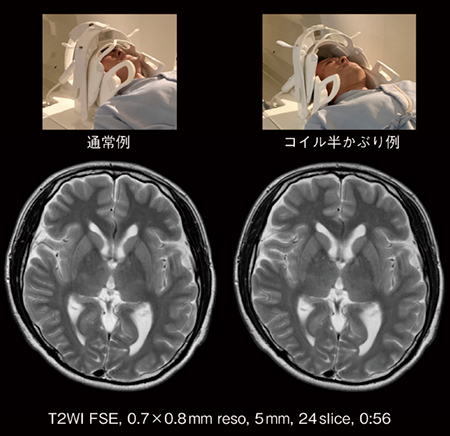

新井:このコイルは,前側のお面を頭頂側から近づけてかぶせていくコイルとなっています。密着することでコイルは視野に入りにくくなるのですが,圧迫感が気になる方では,例えば,マスク部を顔にかぶせず,視界を遮らない状態(Open Head)でも撮像は可能です(図1)。

図1 頭頸部受信コイルの通常例と半かぶり例